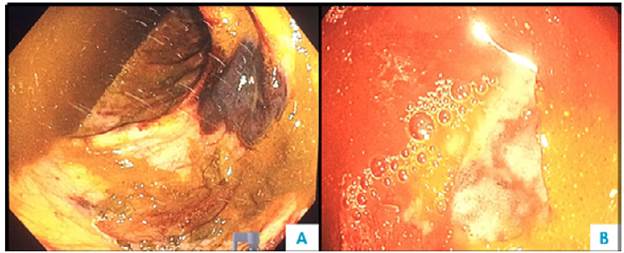

One week after admission, the patient presented acute kidney injury classified as stage 3 KDIGO (discarding prerenal origin, pharmacological toxicity and obstruction) and hypoxemic and hypercapnic respiratory failure, so he was transferred to the intensive care unit (ICU) for invasive mechanical ventilation and initiation of dialysis. Considering the presence of lytic bone lesions and hyperazoemia with nephrotic-range proteinuria by Bence Jones protein filtration, bone marrow aspiration and biopsy were performed, finding 80% of plasma cells (Figure 5). Lambda light chain multiple myeloma ISS III was diagnosed (Table 1). However, a colonoscopy was performed as the patient presented with myopathy, skin lesions, bilateral carpal tunnel, infiltrative cardiomyopathy, hypogonadism, erectile dysfunction and adynamic ileus that were not explained by the myeloma (Figure 6), finding extremely friable mucosa; perineal lesion and renal biopsy were taken to establish the presence of associated systemic amyloidosis.

Colonoscopy. A) Submucosal hematoma and multiple mucosal ecchymoses; B) congestive mucosa and ulcer covered by fibrin.

Figure 6: Colonoscopy. A) Submucosal hematoma and multiple mucosal ecchymoses; B) congestive mucosa and ulcer covered by fibrin.

Source: Own elaboration based on the data obtained in the study.

The patient had gastrointestinal involvement (3.2% frequency) 2; nevertheless, colonoscopy showed ulcerations and friability of the mucosa, classic findings of amyloidosis together with thickening of the intestinal wall, polypoid protuberances, erosions and fine granular appearance of the mucosa. 14 Common symptoms are abdominal pain, esophageal reflux, constipation and nausea. Others include diarrhea, weight loss and early satiety, which may be caused by autonomic neuropathy, bacterial overgrowth or cardiac cachexia. Replacement of intestinal smooth muscle causes dysmotility, pseudo-obstruction and even ischemia secondary to vascular infiltration or ganglion cells depletion. 2 The most involved sites are the duodenum, the rectum and the esophagus. 5,15 Hepatomegaly may be a consequence of congestion or infiltration (by kappa chains, hard and non-pulsatile liver). 3,5 Management is symptomatic with antiemetics, prokinetics and nutritional support 15, but in this case, no medication worked.